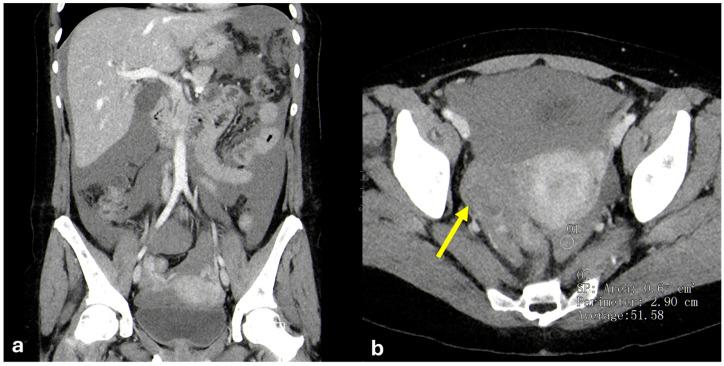

The peritoneum is a thin membrane that lines the abdominal cavity and covers the abdominal organs. It serves as a conduit for the spread of various pathological processes, including gas and fluid collections, inflammation, infections, and neoplastic conditions. Peritoneal carcinomatosis is the most common and well-known pathology involving the peritoneum, typically resulting from the dissemination of gastrointestinal and pelvic malignancies. However, numerous benign and malignant peritoneal diseases can mimic the imaging appearance of peritoneal carcinomatosis. The aim of this review is to revisit the anatomy of peritoneal compartments and elucidate the patterns of peritoneal disease spread. Emphasis is placed on identifying the distinctive imaging features of both neoplastic and non-neoplastic peritoneal diseases that differ from peritoneal carcinomatosis.

腹膜是一层薄的膜,它衬于腹腔内并覆盖腹部器官。它是各种病理过程扩散的通道,包括气体和液体聚集、炎症、感染及肿瘤性疾病。腹膜癌病是涉及腹膜的最常见且广为人知的病理情况,通常由胃肠道和盆腔恶性肿瘤的播散引起。然而,许多良性和恶性腹膜疾病可模仿腹膜癌病的影像学表现。本综述的目的是重新审视腹膜腔室的解剖结构并阐明腹膜疾病的扩散模式。重点在于识别与腹膜癌病不同的肿瘤性和非肿瘤性腹膜疾病的独特影像学特征。